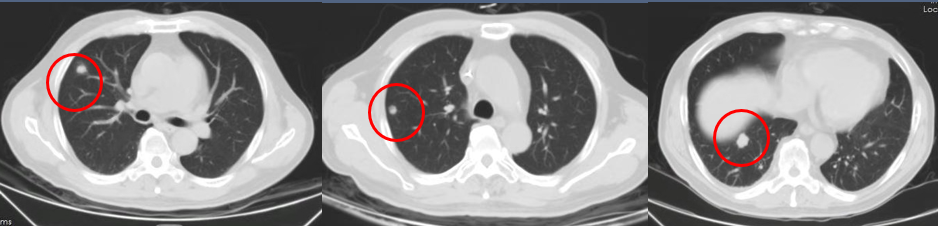

影像评估(PR)

2017.6.6

2017.10.25